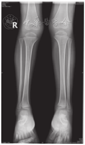

患儿,男,4岁,因"间断腹泻0.5年,皮肤、巩膜黄染5 d"于2017年3月11日就诊于复旦大学附属儿科医院。患儿0.5年前开始反复出现油腻饮食后腹泻,为稀糊便,1~2次/d,无黏液脓血,无发热、腹痛、皮肤黄染,可自行缓解。曾予中成药调理,无明显改善。入院前5 d因体检发现贫血后口服铁剂治疗,渐出现皮肤、巩膜黄染,无发热,不伴腹痛、腹泻及大便颜色变浅,无皮肤瘙痒,无纳差、乏力、恶心、呕吐,小便深黄。发病后曾到当地医院住院治疗2 d,检查发现肝功能异常,贫血、白蛋白低下、凝血功能异常、IgG低下,为进一步诊治,转至复旦大学附属儿科医院。患儿系第1胎,第1产,足月顺产,出生体质量3 650 g,无窒息及抢救史。患儿出生后母乳喂养,按时添加辅食。运动及智力发育与同龄儿相仿;出生后接种卡疫苗后出现左腋下淋巴结脓肿;婴儿期曾2次患重症肺炎并行机械通气。父母体健,非近亲结婚,无明确家族性、遗传性疾病史。体格检查:体质量13 kg,身高95 cm。贫血貌。颈部及腋下可触及黄豆大小淋巴结,皮肤及巩膜中度黄染,无肝掌、蜘蛛痣。心肺查体无特殊,肝脏肋下3 cm,剑突下3 cm,质韧,脾脏肋下未触及。主要实验室检查:血常规白细胞18.4×109/L,嗜酸性粒细胞0.188,血红蛋白84.2 g/L,中性粒细胞0.105,血小板557×109/L,网织红细胞0.064,C反应蛋白64 mg/L;血生化:白蛋白23.9 g/L,碱性磷酸酶171 IU/L,丙氨酸转氨酶132 IU/L,天冬氨酸转氨酶199 IU/L,磷酸肌酸激酶1 710 IU/L,肌酸激酶105 U/L,肌酸激酶同工酶105 IU/L,结合胆红素93.2 μmol/L,γ-谷氨酰转移酶673 IU/L,球蛋白14.7 g/L;钾4.3 mmol/L,乳酸脱氢酶571 IU/L,血氨78 μmol/L;Coomb′s试验阴性;血甲胎蛋白、癌胚抗原、铁蛋白、神经元特异性烯醇化酶均正常;血IgA 0.44 g/L,IgG 2.40 g/L,IgM 0.97 g/L;总IgE 10.0 kU/L;CH50正常,补体C3、C4正常;流式细胞检测CD系列未见明显异常,活化淋巴细胞正常;结核菌T细胞斑点检测(T-SPOT)阴性,血寄生虫抗体阴性,大便常规、隐血及寄生虫检查均未见异常;支气管镜肺泡灌洗液:抗酸杆菌阴性,灌洗液半乳甘露聚糖(GM)试验阴性;腹部磁共振成像(MRI)、磁共振胰胆管成像(MRCP)示肝内胆管、肝总管、胆囊及胆总管扩张(图1);胸部CT示两肺多发斑片、条索状高密度影,局部与邻近胸膜黏连,局部支气管管腔扩张。胸腔见少量积液。骨X线片:双下肢诸骨骨质稀疏(图2);肝脏病理:肝细胞肿胀,部分气球样变,部分肝细胞胞质内见小空泡形成,少量肝细胞内胆汁淤积;部分肝血窦轻度扩张,枯否细胞轻度增生;汇管区纤维组织增生,胆小管增生,部分大胆管周围纤维组织增生,较多嗜酸性粒细胞及少量淋巴细胞、中性粒细胞浸润(图3)。胃镜及小肠胶囊内镜提示浅表性胃炎(轻度),小肠黏膜炎;胃窦黏膜病理活检:轻度慢性炎症,幽门螺杆菌(-)。骨髓涂片未见明显异常。入院后积极给予无脂且蛋白以植物蛋白为主饮食,头孢曲松抗感染,静脉丙种球蛋白、白蛋白、补充脂溶性维生素支持治疗,熊去氧胆酸利胆,患儿腹泻、胆汁淤积好转。获得患儿监护人知情同意后对患儿家系进行高通量测序发现,患儿CD40LG基因突变(exon5 c.506A>G,p.Y169C),169位氨基酸有酪氨酸变为半胱氨酸,为致病性突变(rs786205606),母亲为携带者,为已知X连锁隐性遗传性疾病致病性基因突变。